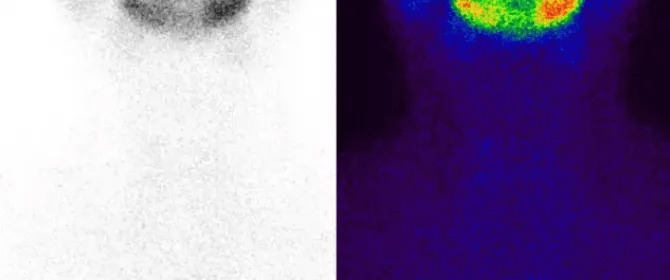

文章图片

(亚急性甲状腺炎影像)

“亚甲炎”的实验室检查发现可随疾病的节段而异 。 早期 , 红细胞沉降率明显增快 , 甲状腺摄131碘率明显降低 , 甲状腺扫描提示甲状腺摄取功能弥漫性或局限性降低 , 但血清甲状腺激素FT3、FT4可暂时性增高 , 主要由于甲状腺滤泡破坏 , 激素外溢所致(以上称为甲状腺激素水平增高和摄取功能减低的“分离现象”) 。 以后 , 由于甲状腺内激素减少 , 血清FT3与FT4降低 , TSH增高 。 随着疾病的好转 , 甲状腺摄131碘率与血清FT3、FT4等均可恢复正常 。